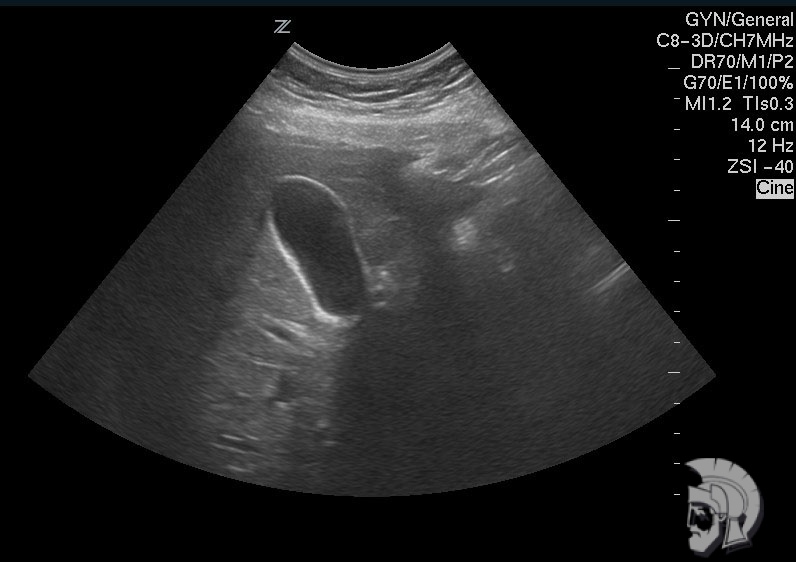

| Фото желчного пузыря. Желчный пузырь с перетяжкой у мужчины 48 лет |

Обратите внимание на совершенное качество фотографий, свидетельствующих об экспертном классе наших аппаратов УЗИ!

Использование ультразвуковых аппаратов экспертного класса с режимами энергетического ДОППЛЕРа и цветового допплера позволяет врачам Курортной клиники мужского здоровья выявлять патологические изменения на ранних этапах.